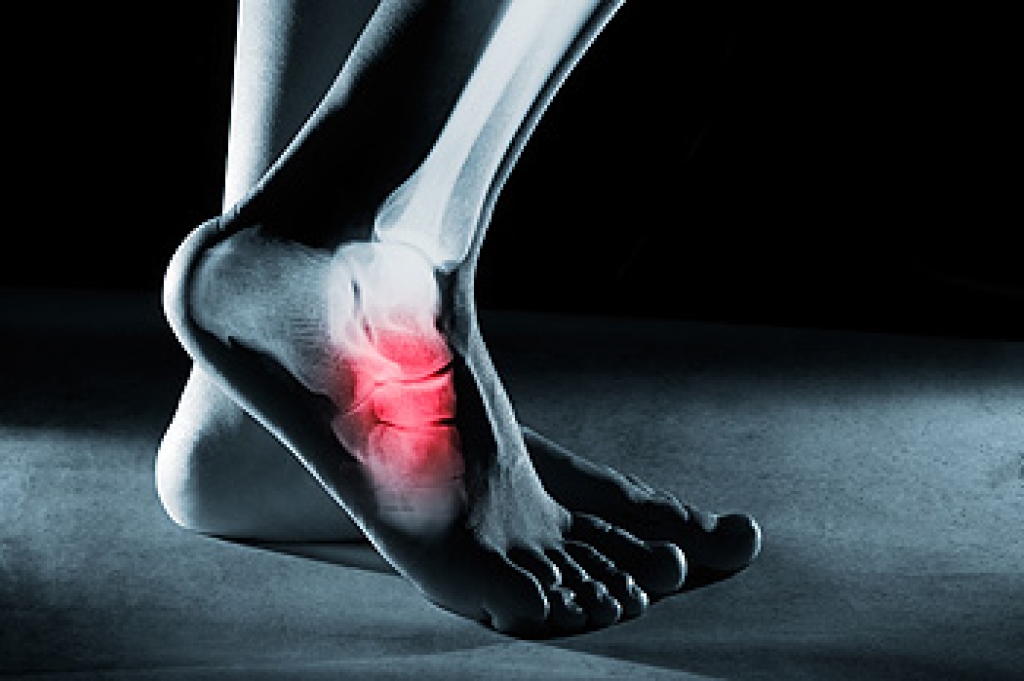

A calcium deposit that forms between the arch of the foot and the heel is referred to as a heel spur. Common symptoms can include heel pain first thing in the morning, followed by a dull ache for the rest of the day. Some patients notice swelling at the front of the heel, and it may feel warm. The heel spur will be visible on an X-ray, and this is a necessary test to have in determining what the proper treatment is. Heel spurs can develop as a result of the aging process when the soft tissue wears thin. People who frequently run may experience this condition, as the heel pad loses shock absorption. Relief may come from elevating the affected foot as often as possible, and this can help to reduce swelling. Additionally, wearing shoes that have a cushion may help to ease the pain that can come from having a heel spur. Many patients who have heel spurs find it is difficult to complete daily activities. If this applies to you or someone you know, it is strongly suggested that you consult with a podiatrist.

Heel spurs are formed by calcium deposits on the back of the foot where the heel is. This can also be caused by small fragments of bone breaking off one section of the foot, attaching onto the back of the foot. Heel spurs can also be bone growth on the back of the foot and may grow in the direction of the arch of the foot.